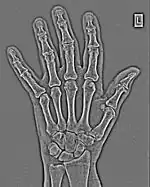

FFTs can also be calculated in two-dimensions to give results such as those in Figure 1.27. Since Fourier analysis generates results in terms of both positive and negative spatial frequencies, these can be plotted in the form of a 2D image so that the maximum frequency lies at the origin and those for the horizontal and vertical directions are shown increasing towards that origin. The modulation at different spatial frequencies is represented using a grey-scale. Low frequency bands can be seen along the horizontal axis in the figure, for example, representing the horizontal periodicity of image data from the fingers, while finer bands along the y-dimension are indicative of a periodicity of image data from the various metacarpophalangeal joints. Higher frequency features can also be seen running diagonally in this 2D-FFT, representative of the trabecular structure of the bones, for example.

The essence of this approach is that it can be used to produce a range of image processing effects by enhancing and/or suppressing features in the 2D-FFT and then converting the result back into the spatial domain using the IFT, as illustrated in Figure 1.28. Such image manipulations are considered in more detail in a later chapter. Note that the form of image processing demonstrated in the figure is for purely illustrative purposes and bears no direct medical significance.

![]() Fig. 1.28(a): A radiograph of the wrist. | ![]() Fig. 1.28(b): The wrist radiograph processed by attenuating periodic structures of size between 1 and 10 pixels. |